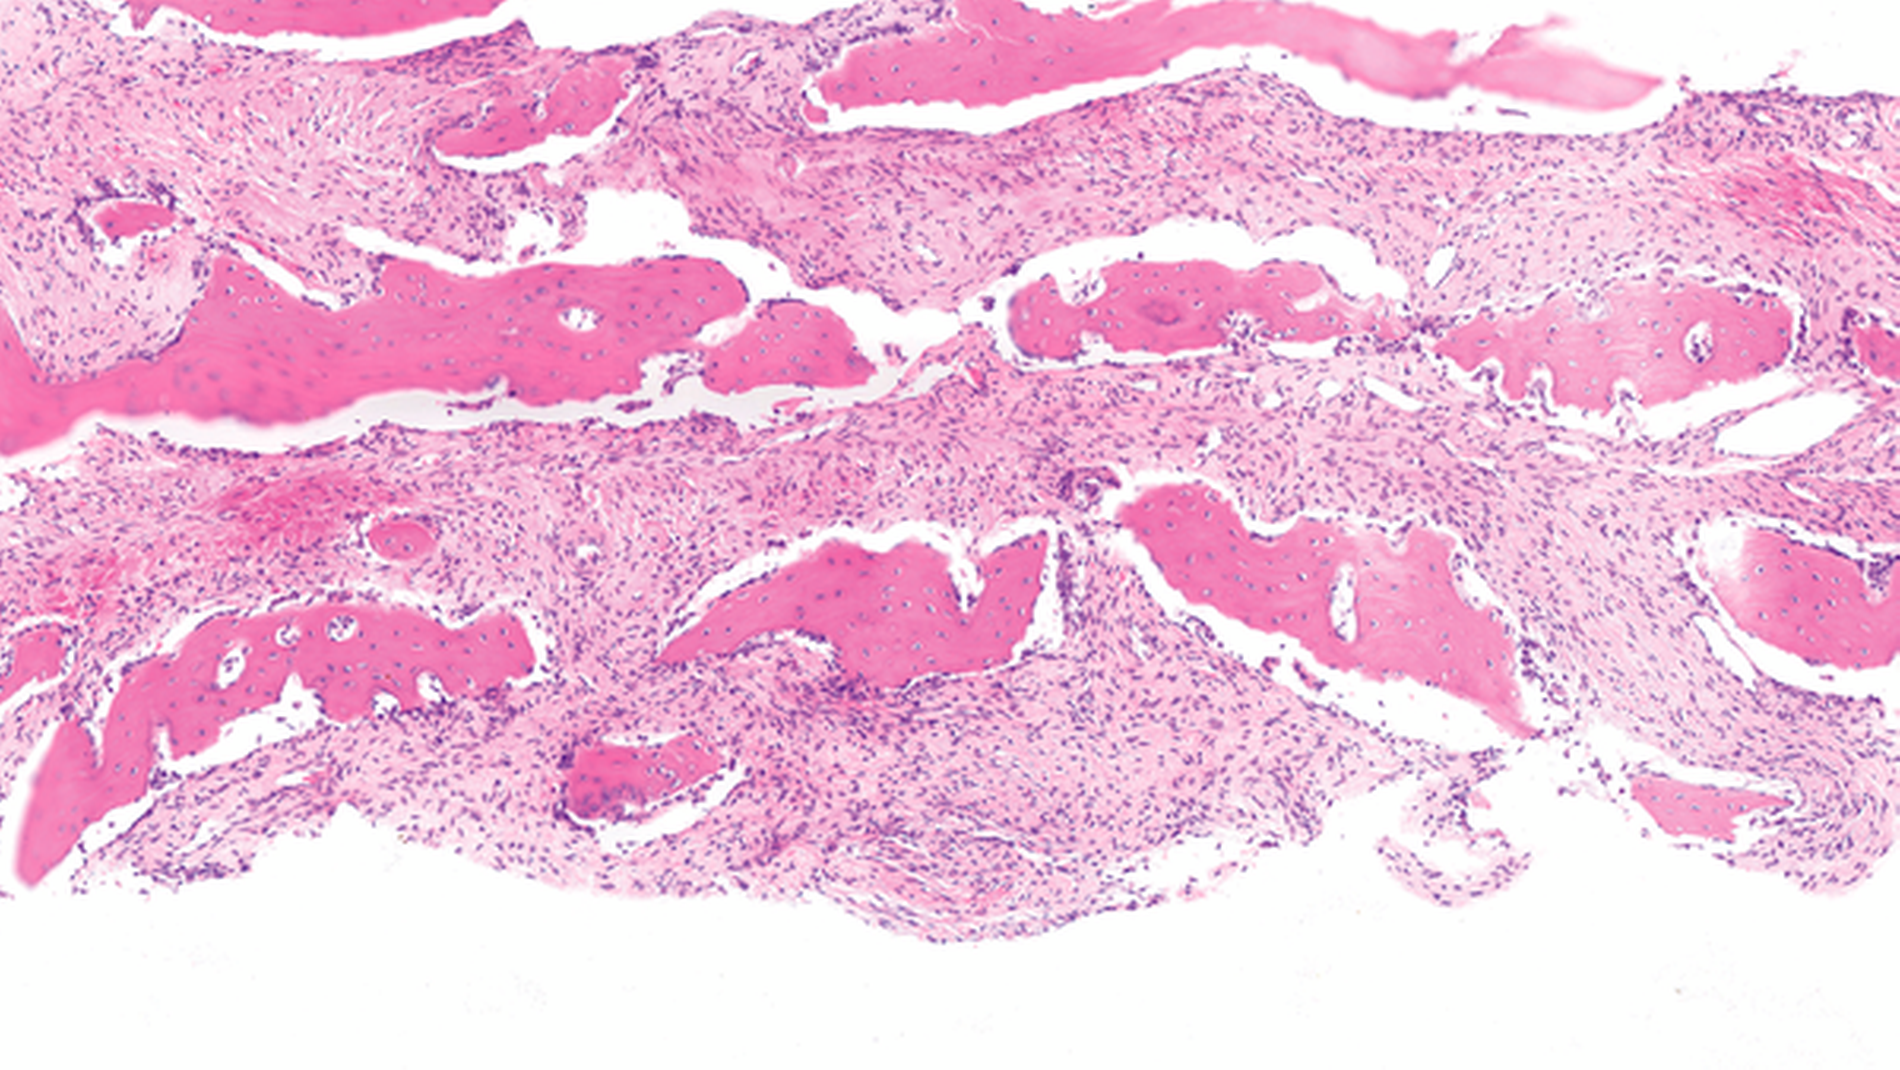

Histologisch (Abbildung 5) zeigte sich eine monomorphe fibro-ossäre Läsion bestehend aus einem reifen und fibroblastären Spindelzellstroma und neu gebildeten Geflechtknochenbälkchen. Die Matrix zeigte Zeichen der lamellären Ausreifung und stellenweise Osteoblasten auf ihrer Oberfläche als Zeichen eines bereits begonnenen reaktiven Remodellings. Im Kontext der Bildgebung wurde die Diagnose einer kraniofazialen fibrösen Dysplasie gestellt.

Histologisch findet sich ein charakteristisches, reifes Spindelzellstroma, das unreife Geflechtknochenformationen einschließt. Die neu gebildete Matrix kann an chinesische Schriftzeichen erinnern und bildet häufig unvollständige Spangen aus. In der Bindegewebsfärbung (zum Beispiel van Gieson) lassen sich radiär aus den Bälkchen ins Stroma ausstrahlende Sharpey’sche Fasern nachvollziehen, typischerweise fehlen auf der Bälkchenoberfläche kubische Osteoblastensäume. Über die Zeit kommt es aber zu regressiven Veränderungen des Befunds und Remodellierungsprozesse setzen ein, bei denen die läsionalen Bälkchen lamellär umgebaut werden und auf ihrer Oberfläche Osteoblasten erkennen lassen. Genetisch liegt der fibrösen Dysplasie eine postzygotische Mutation im GNAS-Gen zugrunde, deren Nachweis in diagnostisch schwierigen Fällen hilfreich sein kann.